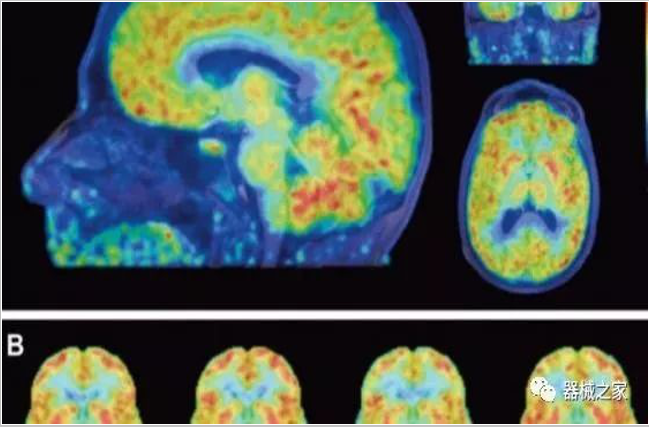

2019年12月19日,國家藥監(jiān)局發(fā)布消息,近日國家藥監(jiān)局批準(zhǔn)上海聯(lián)影醫(yī)療科技有限公司研制的創(chuàng)新醫(yī)療器械 “正電子發(fā)射及X射線計(jì)算機(jī)斷層成像掃描系統(tǒng)”。

正電子發(fā)射型斷層儀(Positron Emission Tomography, PET)是對(duì)正電子示蹤劑的探測(cè)設(shè)備,具有極高靈敏度和精準(zhǔn)的定量功能。而PET/CT是將PET與CT有機(jī)結(jié)合起來的融合設(shè)備,已經(jīng)成為腫瘤、神經(jīng)和心血管系統(tǒng)疾病診斷,臨床分期和療效評(píng)估的最佳影像技術(shù)。